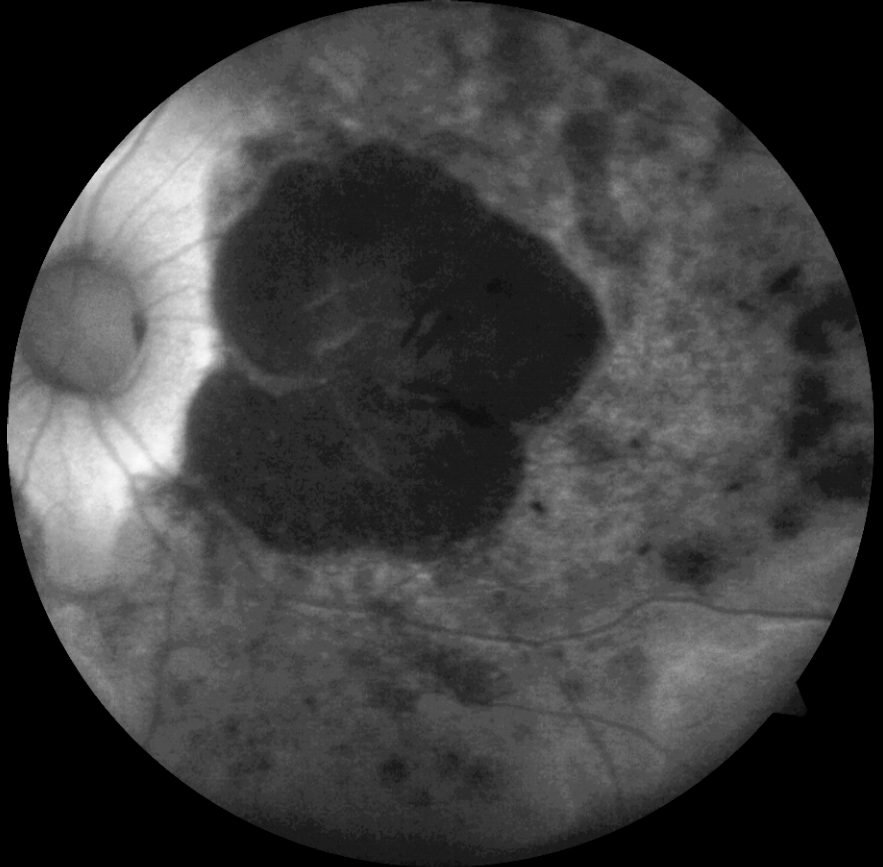

14 yaşındaki erkek hasta bebeklikten bu yana görme kaybı öyküsü ile kliniğimize başvurmuştur. Ailenin tek çocuğudur, anne baba arasında akraba evliliği öyküsü mevcuttur ve her iki gözde görme 1 mps düzeyindedir. Hastanın renkli fundus, FAF ve OCT görüntülerini görmektesiniz. Lütfen cevabınızı aşağıya yazınız.